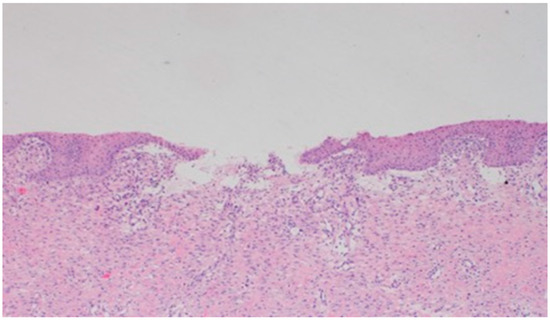

On day 10, all wounds in the control and experimental groups were characterized by a moderate inflammatory infiltration, with a predominance of granulocytes, reaching the dermis. In the experimental group D1, inflammation was at the same level as on the 5th control day. The experimental group D2 and the control group K, treated successively with the 1% nanosilver ointment and sulfathiazole, showed a greater intensity of inflammation in relation to the 5th control day. In group D3, treated with a mixture of 1% propolis and 1% nanosilver, a regression of the inflammatory infiltration, from large to medium, and depth, from adipose tissue to the dermis, was observed. In the experimental group D1, treated with the 1% propolis ointment and control K, treated with sulfathiazole, on day 10, a slight epidermization appeared. On day 10, additionally, all the wounds from the experimental and control groups showed slight superficial necrosis and were characterized by a moderate neovascularization. The histopathological findings from day 10 are presented in Table 9 and Figure 15, Figure 16 and Figure 17.

No epidermization, with slight necrosis (40×, H-E) in the wound treated with the ointment with 1% propolis and 1% nanosilver, on day 10.